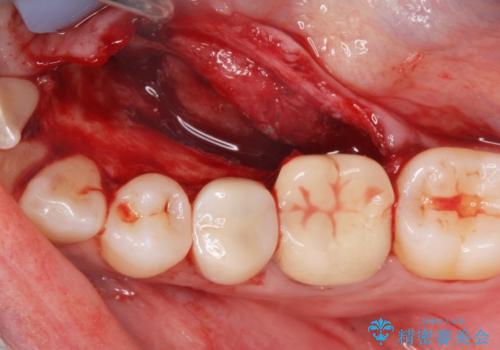

骨隆起除去

- 骨隆起が舌にあたり不快感があるので骨隆起をとりたくて来院。

静脈内鎮静麻酔下で骨隆起を除去を行いました。

骨隆起がなくなり不快感がなくなり大変満足して頂けました。